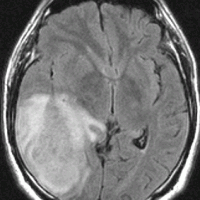

左から、T2強調画像,MRIのFLAIRフレア像,ガドリニウム増強像です。

- フレアとT2で白くぼーっとみえるところは腫瘍のある場所です。腫瘍周辺の脳浮腫も白く映ることがあります。グレード4の膠芽腫では,ガドリニウムという造影剤を使うと右側の写真のように,腫瘍の内部が白く強く増強されます。グレード3ではガドリニウムで増強されないものもあります。びまん性星細胞腫と同様に,実際にはこのMRIで映って見える領域より腫瘍は広い範囲に浸潤して広がっていると考えなければなりません。